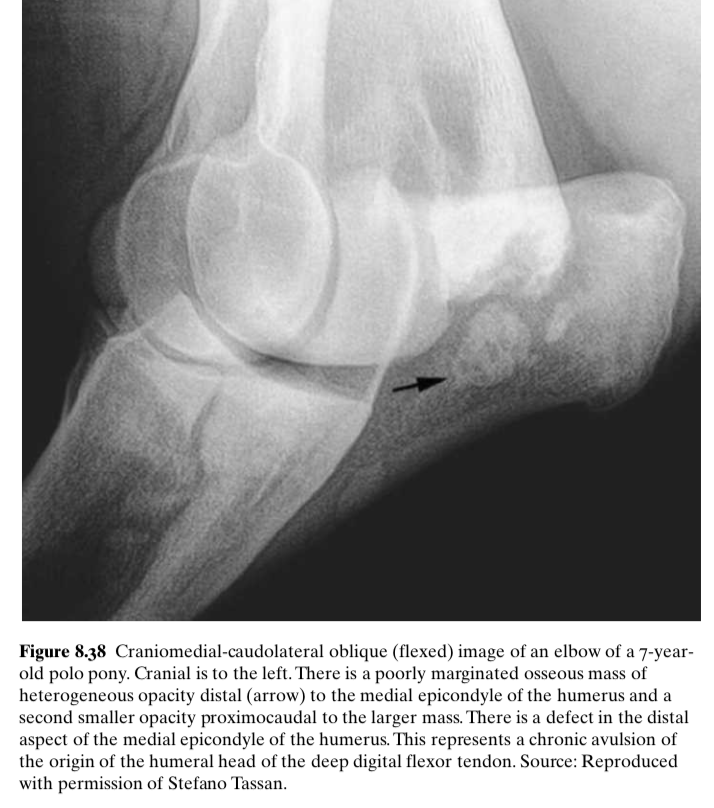

What origonates at the medial humeral epicondyle

Humeral head of the DDFT

What injury can cause this radiographic appearance?

Avulsion of the humeral head of the DDF